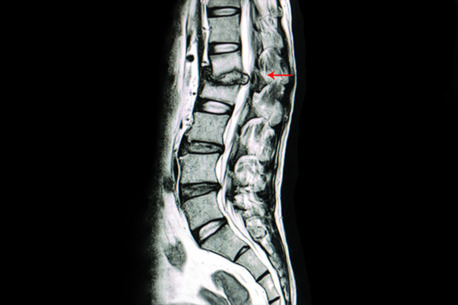

If you are looking for the Best scoliosis doctor in Vizag, consulting an experienced spine expert is essential for accurate diagnosis and effective treatment. Dr. B. Leela Prasad is widely recognized as one of the most trusted specialists for Scoliosis treatment in Visakhapatnam. With extensive experience in treating spinal deformities, he offers advanced diagnostic methods and personalized care for patients of all ages. As a leading Spine specialist for scoliosis in Vizag, he focuses on early detection and modern treatment approaches to help patients improve posture, reduce pain, and maintain spinal health.

Patients suffering from spinal curvature problems can benefit from comprehensive Scoliosis treatment in Visakhapatnam that includes both non-surgical and surgical options depending on the severity of the condition. As the Best scoliosis doctor in Vizag, Dr. B. Leela Prasad provides specialized care, advanced spine correction procedures, and long-term rehabilitation guidance. If you are searching for a reliable Spine specialist for scoliosis in Vizag, visiting his clinic can help you receive expert consultation and the most suitable treatment plan for better spine alignment and improved quality of life.